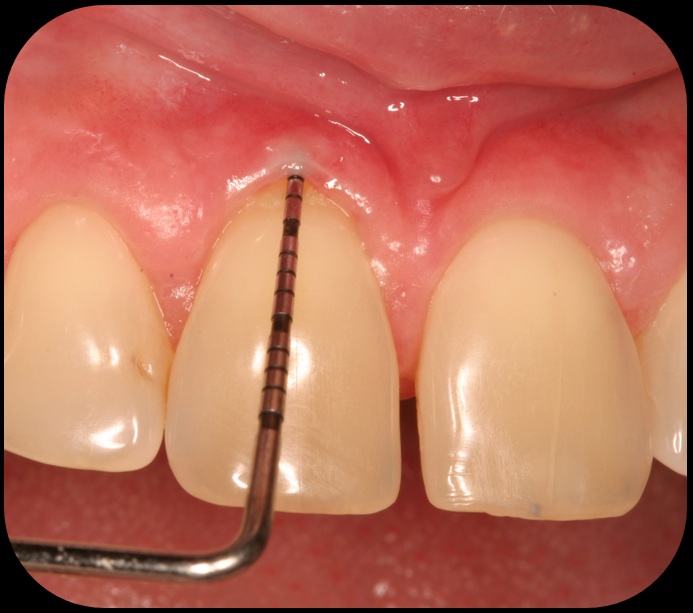

Evidence of clinical attachment gain.

Fig. 6

The 9-year postoperative radiograph.

Fig. 7

Preoperative recession.

Fig. 8

Then, too, are opportunities to prepare the site for regeneration by coupling therapies, applying an enamel matrix derivative, along with traditional bone grafts of demineralized freeze-dried bone allograft; potentially, gains in attachment with minimal probing depth and retained papilla may avoid the need for an implant (Figure 2 through Figure 7).

In the coming decades, restorative treatment for aging patients who experience facial growth with recession and erosion below the cemento-enamel junction because of tooth movement may be especially challenging. However, if dentists can employ the tenets of regeneration using autogenous tissues or a cellular dermal matrix combined with enamel matrix derivatives as a regulatory protein, they may predictably achieve large amounts of root coverage with thickened periodontium. This would not eliminate the need for restorative dentistry, but would enable restorative dentists to place restorations that are supragingival and are easily accessible for the patient and the therapist during maintenance (Figure 8 through Figure 10).